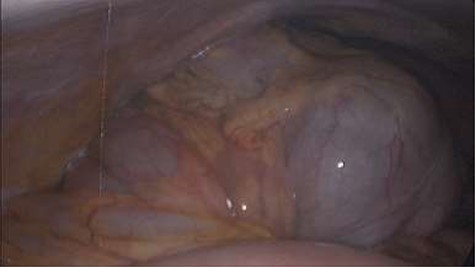

Emergency diagnostic laparoscopy was performed and findings were: 180 degree volvulus of terminal ileum, cecum and ascending colon overlapped each other and overriding the right loop of the liver, the lateral attachment of the right colon was long dilated and floppy (Figs 5 and 6). The dudeno-jejenal flexure was malrotated and lying in left upper quadrant just below to splenic flexure. Three congenital bands were found tilted around the terminal ileum, cecum and base of the appendix. Turbid free fluids with no evidence of infection also noted in the right upper quadrant and right para-colic gutter (Fig. 7). Otherwise, bowels were found healthy and viable. A healthy retrocecal and subserosal appendix was also noted intraoperatively. We converted to open Laparotomy and proceeded with right hemicolectomy due to complex intraoperative findings. The postoperative period was uneventful, and patient was discharged at home on postoperative Day 7.

Showing 180 degree volvulus of terminal ileum, cecum and ascending colon overlapped each other and overriding the right loop of the liver.